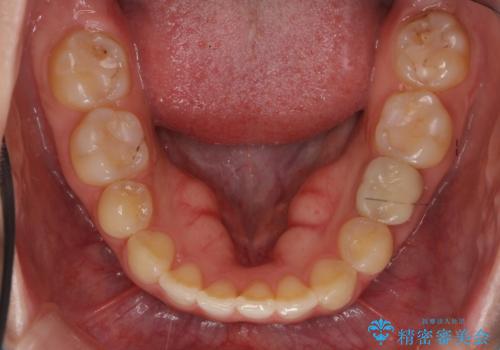

前歯のねじれ 乳歯を残して矯正治療

- 前歯のねじれを気にして来院。

左下に乳歯が残っていましたが、被せ物に穴が空いている状態でした。

乳歯は抜かずに保存的な治療を行いました。

上下の正中が1本分ずれていましたが、ちょうど1本分で目立たず、また、右下の歯が生まれつき少ないことを利用して、最小限の歯の移動にとどめました。

乳歯はまだぐらついたりしていない状態だったため、しっかり虫歯を取り、根の治療も行いました。